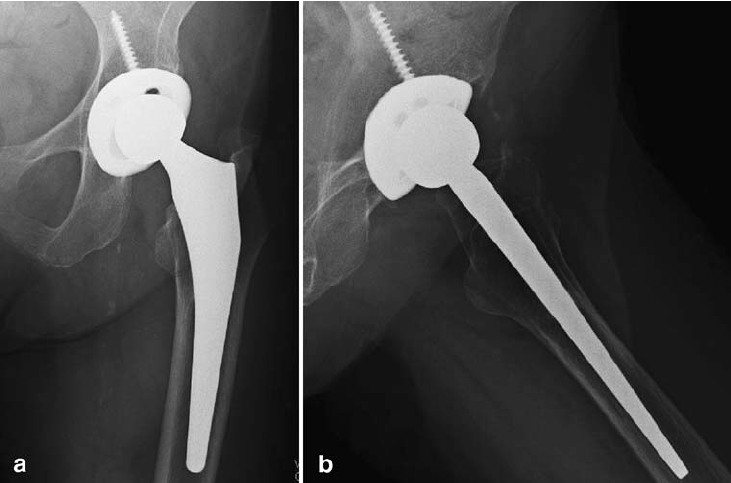

Lower Extremity

The lower extremity refers to the part of the human body that includes the hip, thigh, knee, leg, ankle, and foot. It is essential for weight-bearing, balance, and movement, enabling activities like walking, running, and jumping. The lower extremity consists of major bones such as the femur, tibia, and fibula, along with muscles, ligaments, tendons, and joints that provide strength and flexibility. Injuries or conditions affecting the lower extremity, such as fractures, arthritis, or nerve damage, can severely impact mobility and quality of life. Medical treatments, including physical therapy, surgery, and prosthetics, help restore function and improve movement in cases of impairment.